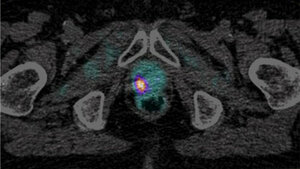

Nuklearmedizin